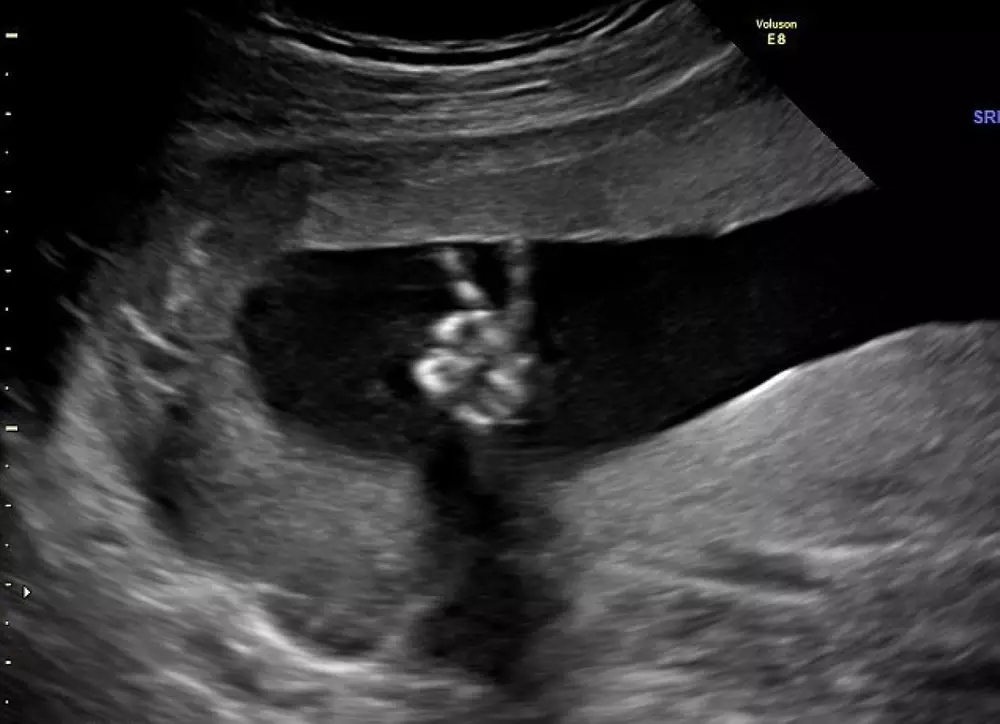

Когда беременная англичанка Ди Парсонс отправилась вместе с мужем Эдом на плановое УЗИ, то не ожидала увидеть на снимке ничего принципиально нового. Однако взглянув на готовую фотографию, 35-летняя женщина обомлела - ее 20- недельный малыш показывал родителям дерзкий жест "победы", пишет британская газета Daily Mail.

Сотрудница больницы, проводившая ультразвуковое обследование, также немало удивилась. По ее словам, она никогда не видела ничего подобного.

© GEORGIE GILLARD